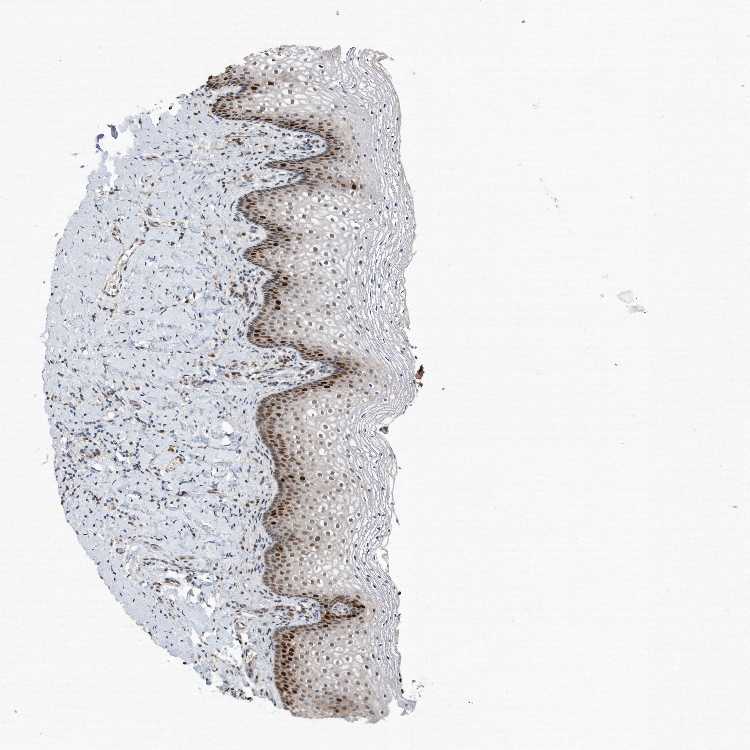

TISSUE PRIMARY DATA VAGINA Show tissue menu

Vagina

VAGINA - Expression summary

Protein expression

On the top, protein expression in current human tissue, based on all annotated cell types, is reported with the units not detected (n), low (l), medium (m) and high (h). Underneath, protein expression in each annotated cell type are reported using the same units.

Protein expression data is based on knowledge-based annotation. For genes where more than one antibody has been used, a collective score is set.

If knowledge-based annotation could not be performed for a gene, no data is displayed here. View antibody staining data further down this page.

Squamous epithelial cells: Medium

VAGINA - Antibody stainingi

Antibody staining in the annotated cell types in the current human tissue is reported as not detected, low, medium, or high, based on conventional immunohistochemistry profiling in selected tissues. This score is based on the combination of the staining intensity and fraction of stained cells.

Each image is clickable and will lead to virtual microscopy that enables deeper exploration of all samples and also displays staining intensity scores, fraction scores and subcellular localization as well as patient and tissue information for each sample.

Antibody HPA030521Antibody HPA030522Antibody HPA030523Antibody CAB000148Antibody CAB080240Antibody CAB080241Antibody CAB080242

Squamous epithelial cells HighHighMediumNot detectedMediumHighHigh